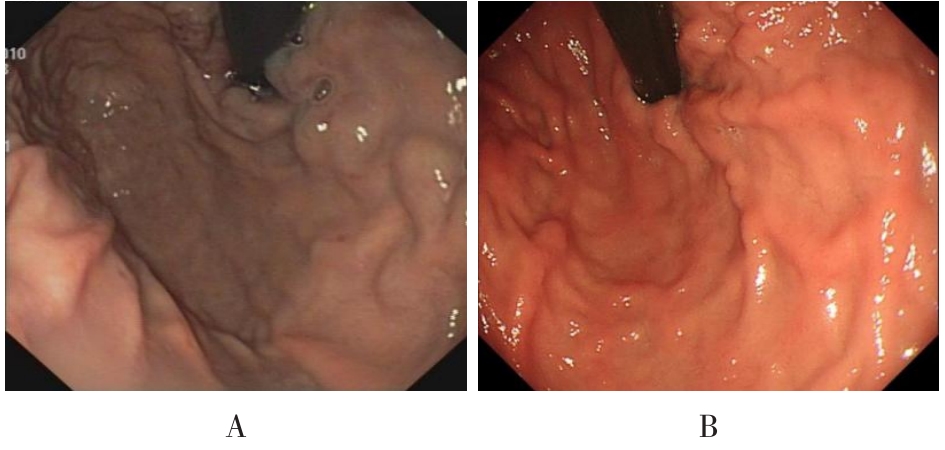

• 获得性免疫缺陷综合征合并马尔尼菲篮状菌导致肠道感染的内镜下表现(附6例报告)

2026, 32(3):84-88. DOI: 10.12235/E20250461

摘要 (32) HTML (27) PDF 3.50 M (26) 评论 (0) 收藏

摘要:目的 探讨获得性免疫缺陷综合征(AIDS)合并马尔尼菲篮状菌(TM)感染导致肠道感染的内镜下特征。方法 回顾性分析2022年11月-2024年10月于该院确诊为AIDS合并TM感染导致肠道感染的6例患者的临床资料。包括:临床症状、实验室检查、影像学检查、内镜检查和病理检查等。结果 6例患者中,男5例,女1例;发病年龄26~67岁;AIDS合并TM感染导致肠道感染患者的临床表现为:腹泻、腹痛、腹胀和恶心呕吐。其中,2例有消化道出血表现。实验室检查:6例患者外周血白细胞计数为(1.37~4.49)×109/L,血红蛋白计数为(67~99)g/L;CD4+T淋巴细胞为(1~52)个/μL,CD8+ T淋巴细胞为(61~321)个/μL,CD4+T淋巴细胞/CD8+T淋巴细胞比值为(0.01~0.18)。6例患者均行HIV RNA检测。其中,5例HIV RNA阳性。血培养:可见丝状真菌,报告显示为TM。影像学检查:6例患者CT结果可见肠系膜及腹膜后多发淋巴结肿大。内镜检查:6例患者内镜下均可见肠道病变。其中,十二指肠糜烂溃疡2例,结肠多发糜烂溃疡4例。病理检查:6例患者幽门螺杆菌(Hp)结果均为阴性,黏膜下可见成簇的小球形真菌孢子,符合TM感染;特殊染色:PAS(+),六胺银染色(+)。结论 当AIDS晚期患者出现消化道症状时,应警惕TM感染,病变部位常见于全结肠和直肠,亦可累及十二指肠,内镜下表现多为溃疡、糜烂和隆起性病变,形态表现无特异性;及时行胃肠镜检查、病理活检、特殊染色和免疫组化是确诊的关键。